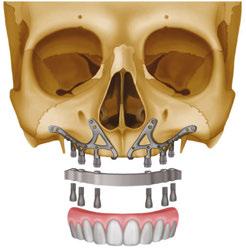

Treatment of severely atrophic maxillae often requires highly advanced procedures such as quad-zygomatic implants1-3 (Figure 1) or customized subperiosteal implants (Figure 2).4,5 Quad-zygomatic implant treatment has a long history of success, but requires significant surgical expertise due to limited malar bone availability and propinquity to anatomic structures such as the orbit and infraorbital nerve.6 Customized subperiosteal implants, on the other hand, are a promising new treatment option but have limited long-term follow-up data and significant expense.7 Transnasal dental implants have recently been introduced as another option for treatment of severely atrophic maxillae, specifically as an alternative to quad-zygomatic implant placement (Figure 3).8 Transnasal implants may serve as a replacement for anterosuperior zygomatic implants as they tangentially traverse the interior lateral nasal wall and achieve high insertion torque via 3 mm-5 mm of apical engagement in the confluence of the inferior concha, lateral nasal wall, and frontal process of the maxilla (Figure 4).8-16

walls, the piriform rim of the nasal aperture, and the nasal crest of the maxilla. Facial buttresses can also be suitable areas of implant anchorage. These include the nasomaxillary, zygomaticomaxillary, and pterygomaxillary buttresses as seen in Figure 3.

Remote anchorage

In cases of severe maxillary atrophy, there are remote sites of implant anchorage that deviate from the traditional sites of the alveolar bone. These remotely anchored implants include pterygoid, trans-sinus, zygomatic, trans-nasal, and subperiosteal implants. These techniques require advanced training due to their increased degree of difficulty and should only be performed when clinically appropriate. Pterygoid, zygomatic, and trans-sinus implants will be generally discussed in this article. These descriptions serve as a basic understanding of these implants. Resources such as Dan Holtzclaw’s Remote Anchorage Solutions for Severe Maxillary Atrophy (Zygoma Partners, LLLP), Carlos Aparicio’s Advanced Zygomatic Implants: The ZAGA Concept (Quintessence Publishing), and many others can be studied if the reader would like a deeper didactic understanding and insight into remotely anchored implants.

Zygomatic implants

Zygomatic implants are significantly longer implants which engage the dense bone of the zygoma and were originally placed to provide posterior support in the severely atrophic maxilla15 (Figure 15). These implants are indicated when there

Figure 12: 3D CBCT rendering

Figure 13 (left): Sagittal slice of pterygoid implant angled in a superior-distal angle. Figure 14 (right): Coronal slice of pterygoid implant angled in a superior-medial direction

Figure 15: 3D CBCT rendering of zygomatic implants. Photo contributed by Dr. Frank Nelson

is little to no remaining bone height of the alveolar ridge as well as severe anterior pneumatization of the maxillary sinuses.15 Carlos Aparicio created the Zygoma Anatomy Guided Approach (ZAGA) in 2011 which serves as a guide for zygomatic implant planning with respect to patient specific anatomy of the zygoma and favorable prosthetic planning.15 As previously mentioned, the zygomaticomaxillary buttress is one of the several buttresses of the skull that provide a mass of cortical bone that can be used for predictable immediate loading. Although predictable, these implants should be reserved for severely atrophic cases and revisions as indicated.

The PATZI protocol is another approach described by Shouvik Ponnusamy, Juan Gonzalez, and Dan Holtzclaw which aims to improve cumulative torque values, AP spread, and prosthetic planning using a systematic algorithm17 (Figure 19). “PATZI” is an acronym for Pterygoid Anterior Tilted Zygomatic Implants. This protocol begins with placement of the pterygoid implant. The next step is implant placement in the anterior. These implants include axial, nasopalatine, piriform rim, or transnasal implants. Next is the placement of the tilted implant. These implants provide support for the mid-maxillary region and consist of either traditional All-on-4 tilted implants or trans-sinus implants. Lastly, if the tilted implants are not able to be placed, zygomatic implants are utilized in this region. As it relates to the implant’s apical position within the zygoma, a posterior-inferiorly placed zygomatic implant can be used for posterior prosthetic support, and an anterior-superiorly placed zygomatic implant can be used for more anterior prosthetic support. The PATZI protocol is a novel approach to mechanically anchoring implants into favorable positions and decreasing/eliminating cantilever stresses with fixed full arch maxillary rehabilitation.